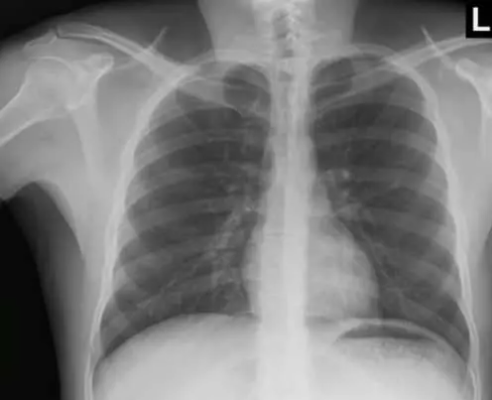

GEÇMEYEN ÖKSÜRÜĞÜ İÇİN DOKTORA BAŞVURDU -

Yerel basında çıkan haberlere göre, Çin'in doğusundaki Zhejiang eyaletinde 54 yaşındaki Xu, geçmeyen öksürüğü için ilaç kullandı.

Bitkisel tedavi yollarına başvurdu. Uyguladığı yöntemlere rağmen hiçbir iyileşme belirtisi göstermeyen Xu, şikayetinin devam etmesi üzerine hastaneye gitmeye karar verdi.